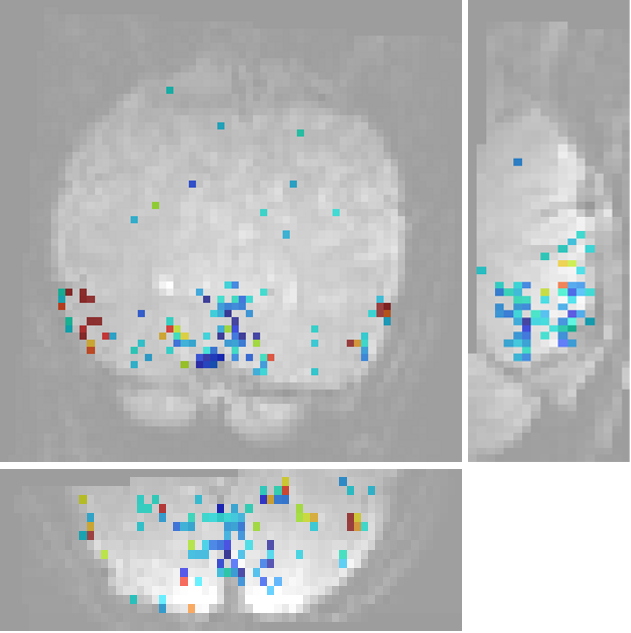

Zero-sum Morlet wavelets improve the fit of first order descriptors to an extent that they compete with second order features in some regions, but are outperformed in others: As can be seen in Fig. 1, there exist spatially contiguous regions largely outside commonly mapped retinotopic areas, in which adding second layer scattering coefficients is beneficial to the model.

We find that an overwhelming majority of the voxels that are well-modelled using first order invariant scattering descriptors is largely better modelled using second order invariant scattering descriptors. The scatterplot 5 indicates this clearly. A Wilcoxon signed rank test provides a confirmation (). Figure 4 shows the localisations of well modelled voxels together with regions that display a high sensitivity to retinotopy. One observes that many voxels outside the low-level ventral visual areas are well modelled by the scattering transform. This includes dorsal regions (up to the intra-parietal sulcus), lateral occipital and medio-temporal regions, and not necessarily retinotopic regions; more precisely several foci are found in V1/V2, and more so in V3 and V4. Blue indicates regions where adding second order features to the first order features does not result in a predictive performance gain. Red indicates regions where one observes a performance gain by adding second order features. The regions were coloured red if the performance gain was greater than of explained variance and blue if the performance gain was or performance decreased. We noticed that the regions that display a strong sensitivity to layer 2, as well as those that actually discriminate between textures, are confined to some foci, the location of which is highly reproducible across sessions and even across subjects.